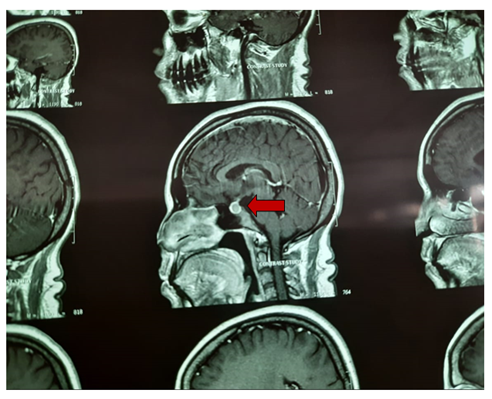

MRI Brain (P+C) showed pituitary gland enlarged with convex superior margin. Enlarged pituitary measured about 11mm in AP, 14mm in lateral and 11mm in cranio-caudal dimensions. Post contrast study showed enhancement there. Infundibulum was central. Radiologist gave impression that MRI findings are suggestive of pituitary macroadenoma.

She was referred to neurology and endocrinology. Endocrinologist gave impression that the pituitary mass was likely macroprolactinoma (densely granulated cell type). And they advised Tab Cabergoline 1 tablet once daily for 2 days in a week and to review after 3 months with serum prolactin and MRI reports. Neurologist also opined the same and suggested for Psychiatry referral for her episodes of loss of consciousness (pseudoseizure). Psychiatrist diagnosed as her having psychogenic non-epileptic seizures as she complained of frequent episodes of unresponsiveness, lasting upto 4hrs during which patient could hear everything but cannot move or respond. They prescribed Escitalopram and Clonazepam tablets. Ophthalmology referral was done to rule out any visual field abnormality although the mass was away from optic chiasma and patient didn’t have any visual symptoms.

Thus with Cabergoline, the symptoms of hyperprolactinemia resolved and the tumour size markedly regressed Figures 1–4.

Figure 2 Closer section of the MRI brain section showing the pituitary macroadenoma-prolactinoma.